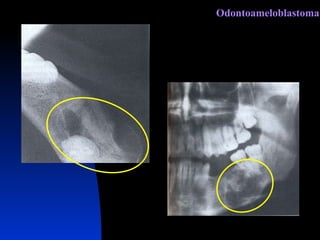

Odontoameloblastoma

C l í n i c a É uma lesão rara, na qual pode-se encontrar um odontoma complexo associado a um ameloblastoma. A histologia é uma mescla de epitélio odontogênico com tecidos dentários, dispostos de forma desordenada. Odontoameloblastoma

R a d i o l o g i a  Imagem radiolúcida Geralmente uniloculada No seu interior, ilhas radiopacas Semelhantes ao odontoma complexo Odontoameloblastoma